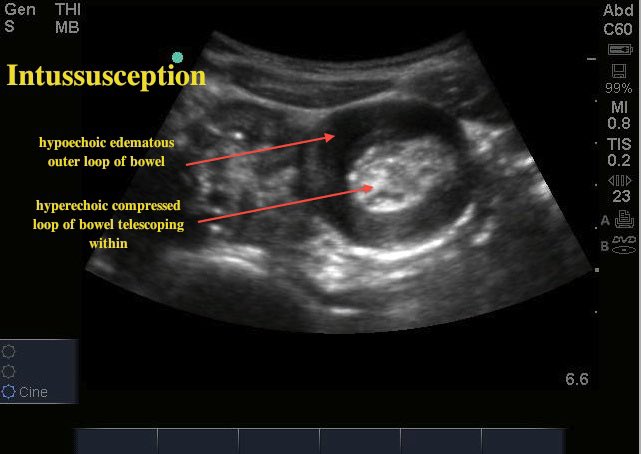

Intussusception